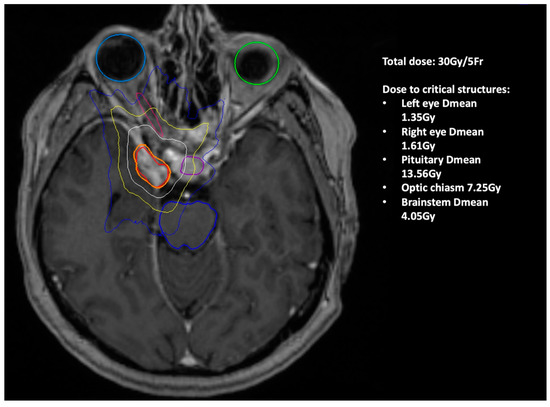

| 1. | F/60 | 30 | 5 | 5.13 | 66 | none | regression |